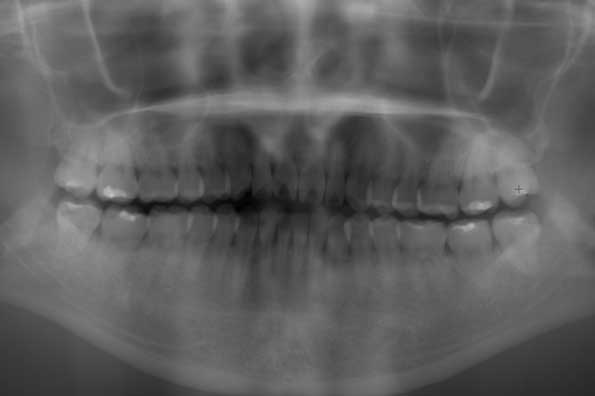

CASE 17

| 年齢・性別 | 18歳・男性 |

| 主訴 | 矯正を開始する前に左下と左上の親知らずを抜きたい |

| 抜歯期間 | 約1時間 |

| 抜歯費用 | 1本22,000円×2本 合計44,000円 (2022年10月現在) |

| 抜歯内容 | 完全埋伏抜歯 |